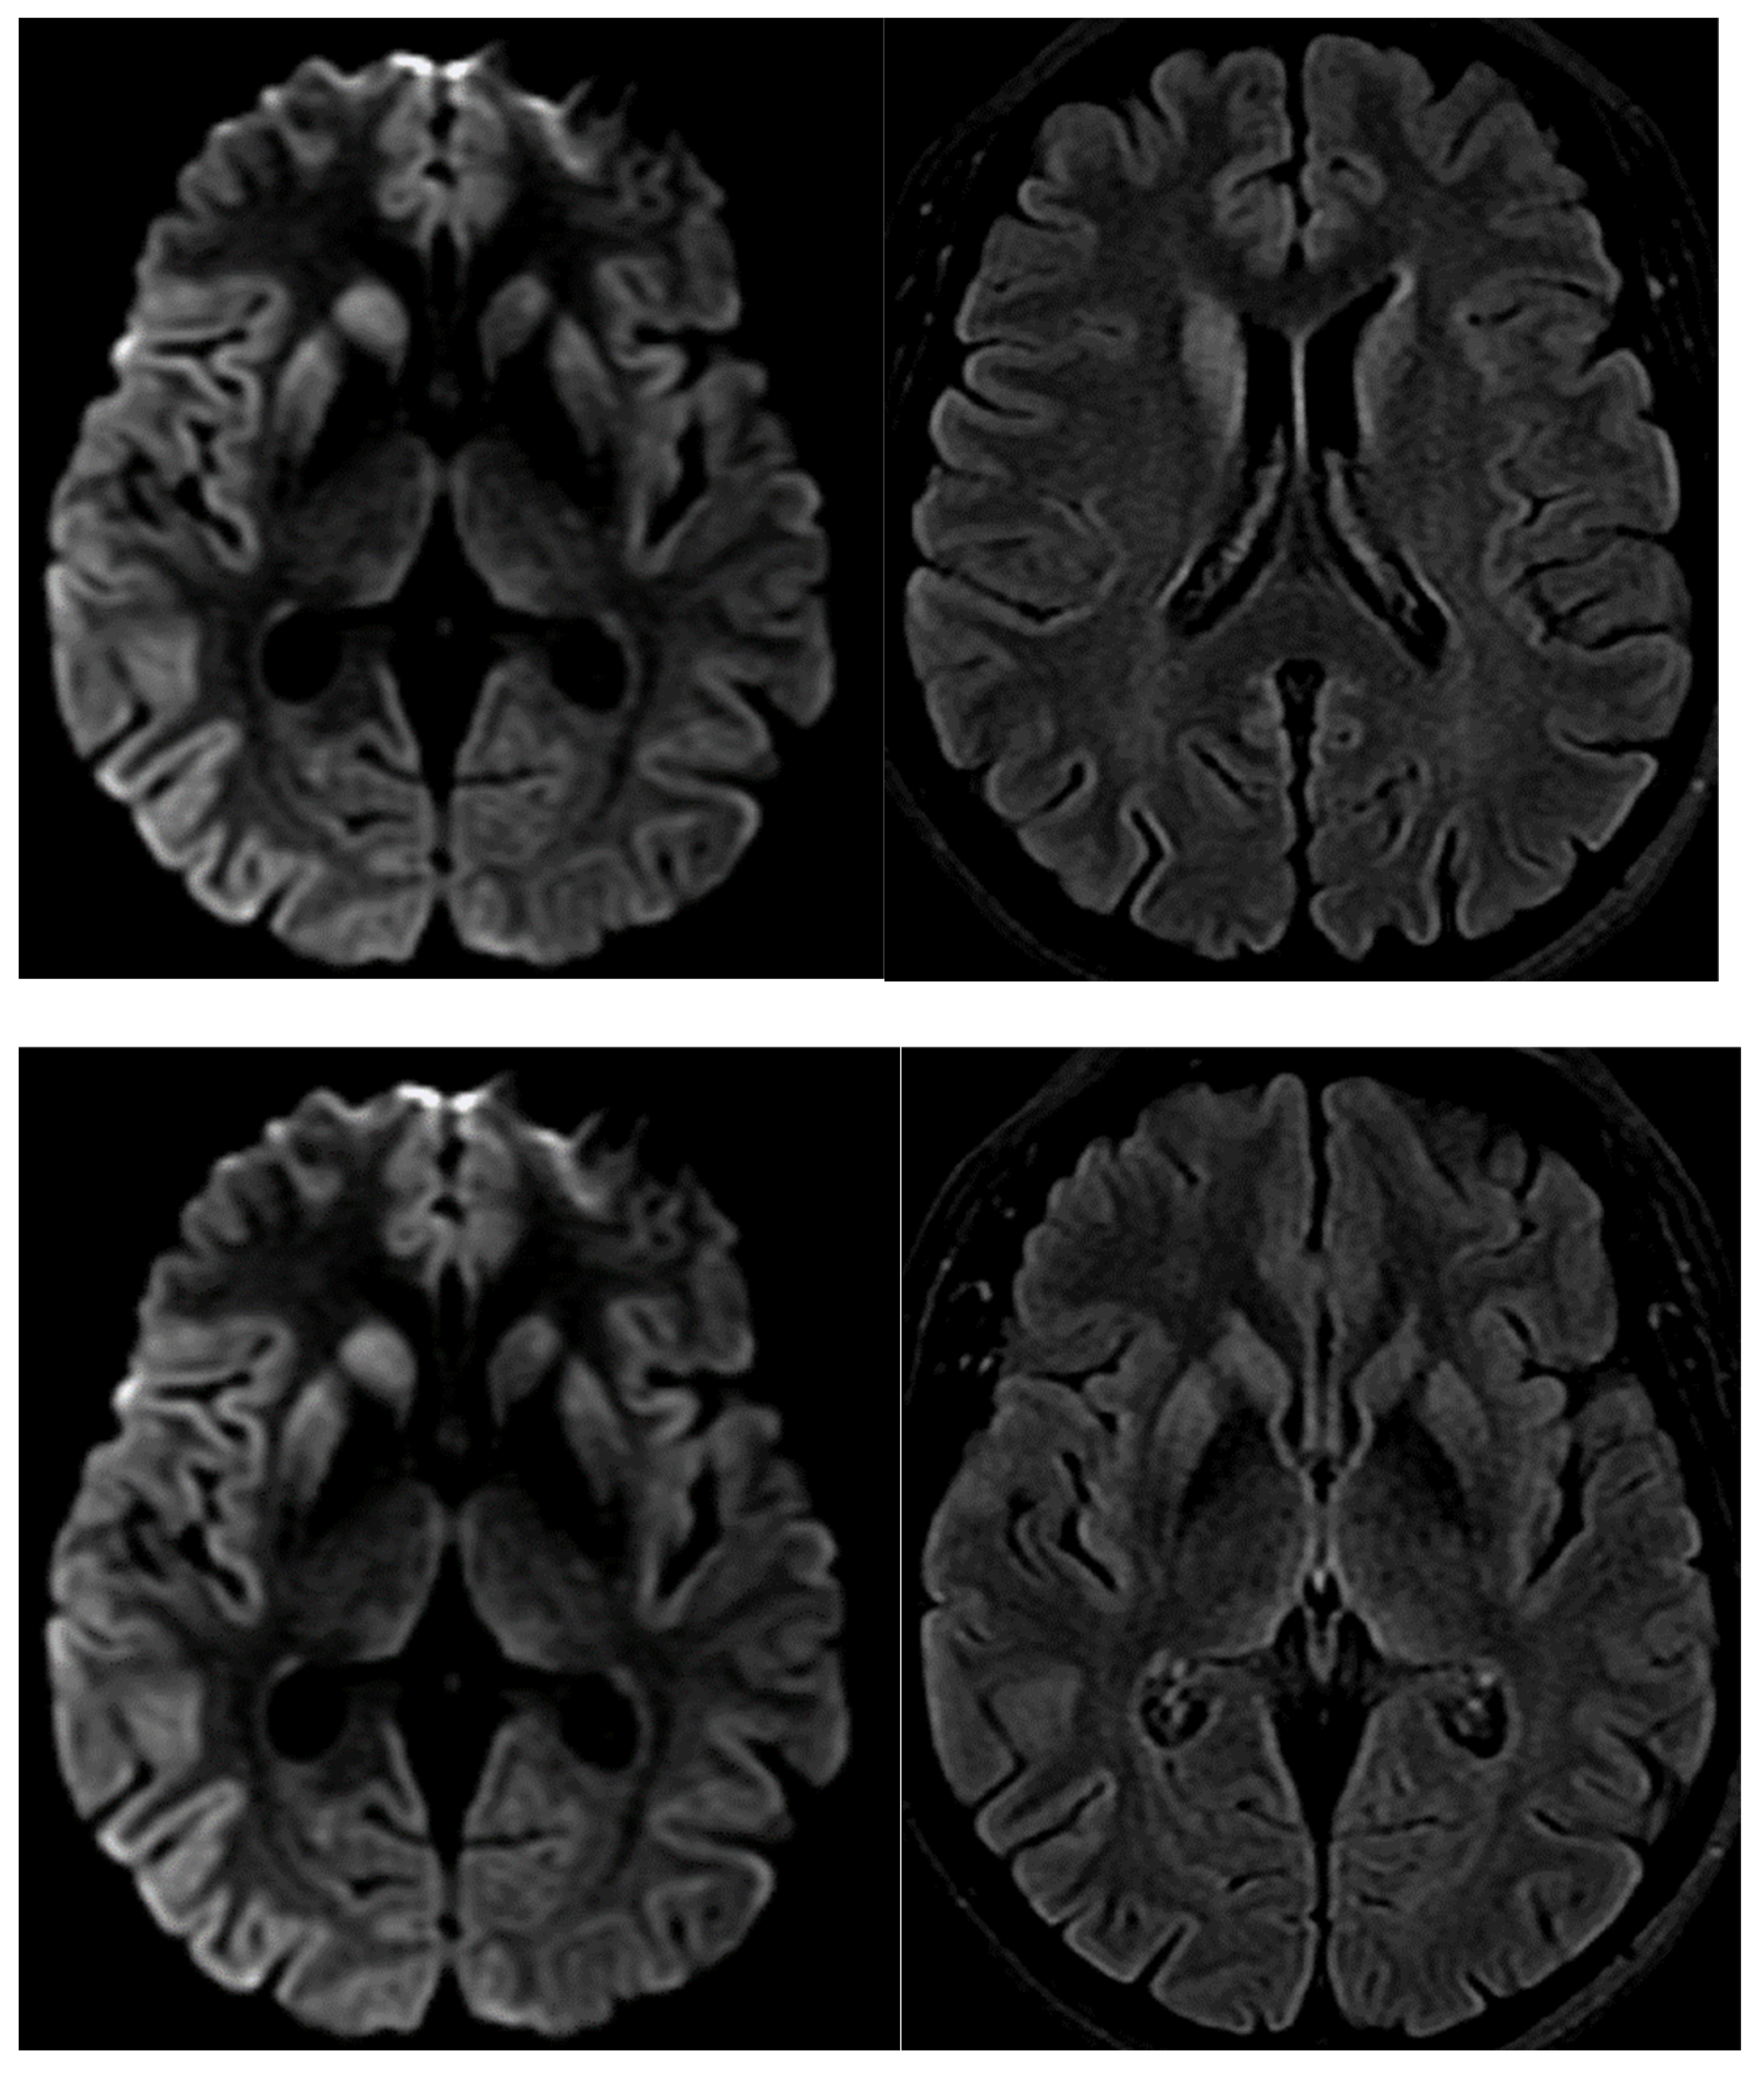

- Fulbright, R.K.; Kingsley, P.B.; Guo, X.; Hoffmann, C.; Kahana, E.; Chapman, J.C.; Prohovnik, I. The imaging appearance of Creutzfeldt–Jakob disease caused by the E200K mutation. Magn. Reson. Imaging 2006, 24, 1121–1129. [Google Scholar] [CrossRef] [PubMed]